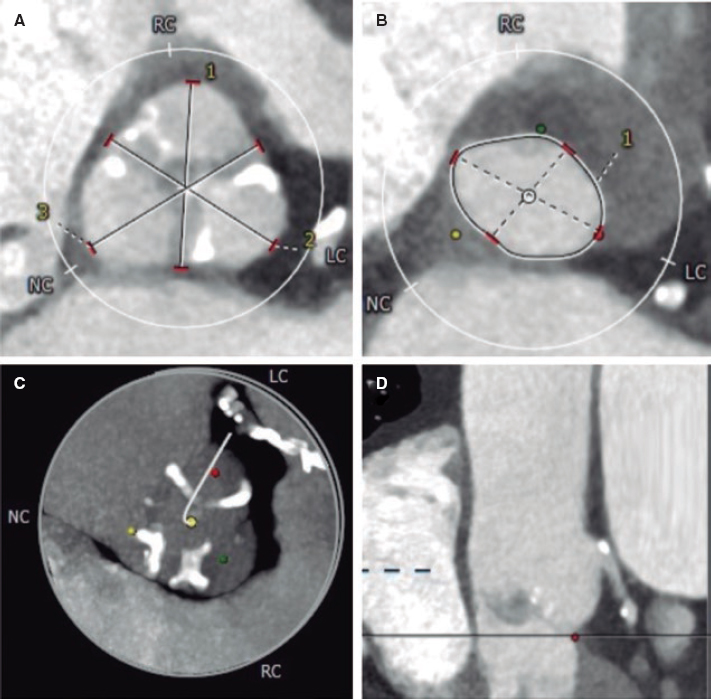

The stent seemed to have been deployed totally outside the right coronary artery, which is why we tried to capture it using a semi- compliant balloon in order to try to drag it towards the radial artery for implantation purposes, but such a maneuver failed (figure 1). This is how we confirmed that the stent was anchored to the ostium by just a few millimeters. Initially the intravascular ultrasound was not used here to assess the location of the stent to avoid any possible moves and manipulations of the implanted stent.

Figure 1. Attempt to drag the stent out of the coronary artery with a semi-compliant balloon.